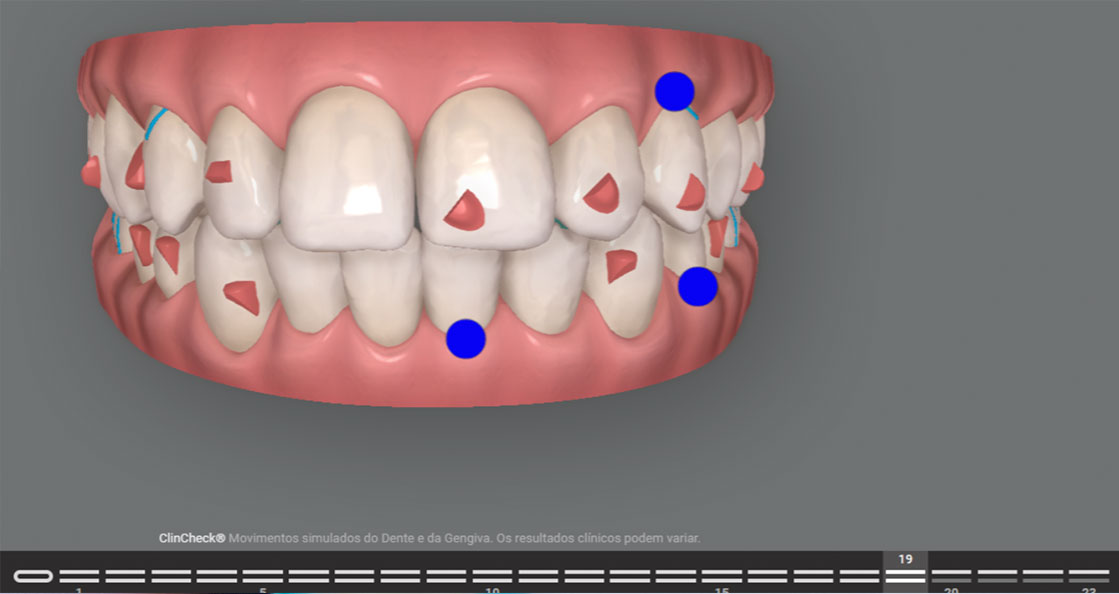

O ClinCheck, que é o software de planejamento do Invisalign, é uma ferramenta poderosa. No entanto, ele não substitui a experiência do ortodontista.

Em um tratamento de excelência, o ortodontista ajusta cada detalhe: inclinações dentárias, torque, sobrecorreções, sequência de movimentos e uso estratégico de attachments e outros dispositivos auxiliares.

Esse refinamento faz com que o resultado planejado seja mais próximo do resultado real, reduzindo a necessidade de correções posteriores.

A movimentação dentária com alinhadores depende de forças sutis e altamente controladas. Em um tratamento comum, essas forças podem não ser totalmente otimizadas.

Já em um tratamento de excelência, há um cuidado especial com a biomecânica: os movimentos são planejados de forma progressiva, respeitando limites biológicos e priorizando previsibilidade.

Isso inclui decisões como quando movimentar determinados dentes, como distribuir as forças e quando utilizar recursos auxiliares, como elásticos, mini-implantes, Power Ridges, Bite Ramps, Carriere Motion, entre outros.